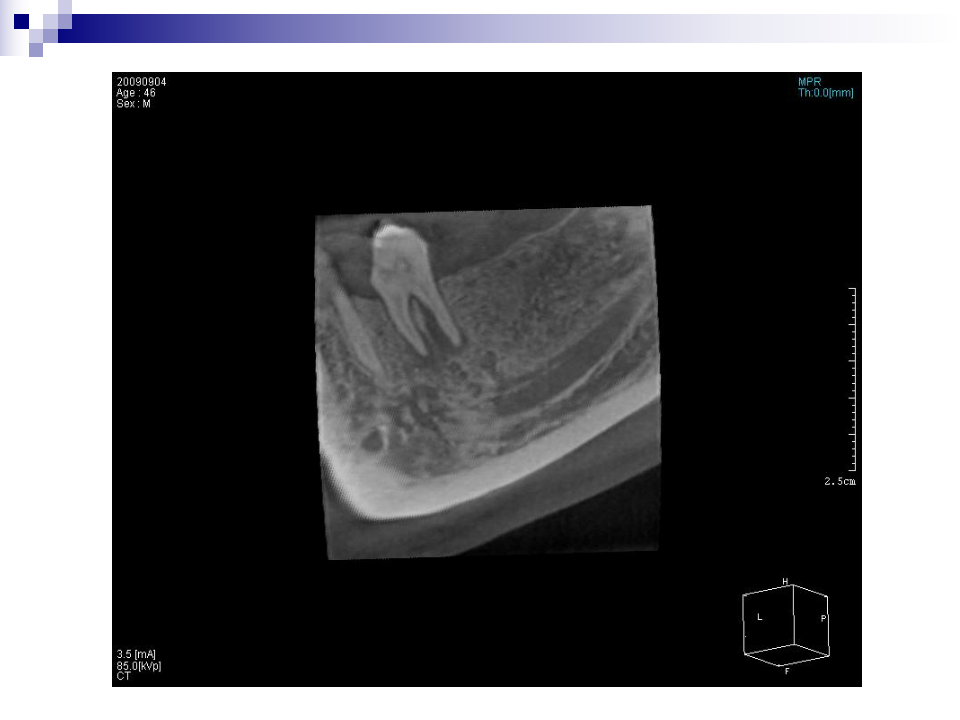

口腔医学

口腔放射

口腔3D影像在口腔种植中的应用.ppt